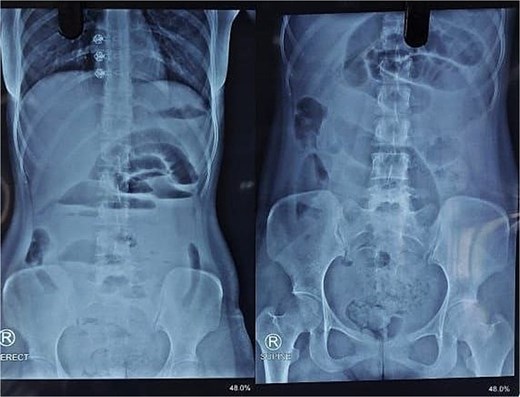

X-ray abdomen showed dilated small bowel loops with faecal loading (Fig. 1). Ultrasound abdomen/pelvis revealed dilated small bowel loops with to-and-fro peristalsis, suggestive of small bowel obstruction. Contrast-enhanced computed tomography (CT) abdomen/pelvis revealed distal ileal thickening causing obstruction, a left iliopsoas abscess communicating with a paravertebral abscess (L5–S2), and erosion of the L5 vertebral body (Figs 2 and 3).

X-ray abdomen showing dilated small bowel loops with faecal loading (erect and supine).